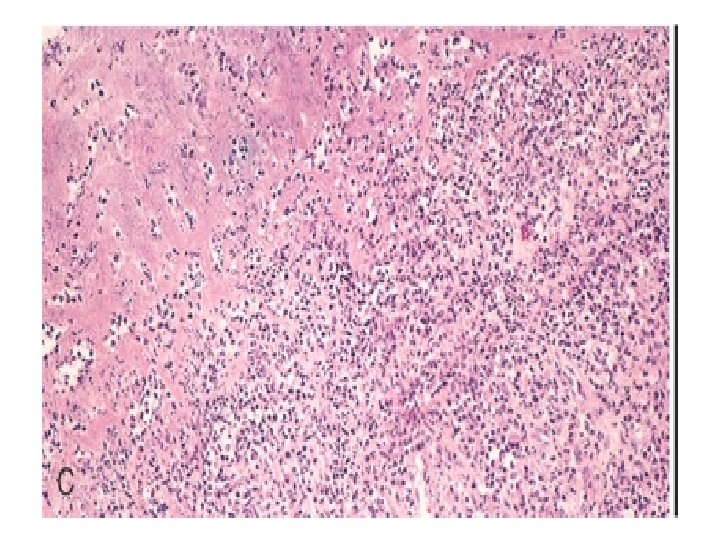

Microscopy - Vegetations 20

• Layer of fibrin & platelets • Bacterial colonies • Inflammatory reaction on the cusp 21

Vegetation in active infective endocarditis- fibrin , neutrophils , monocytes 24